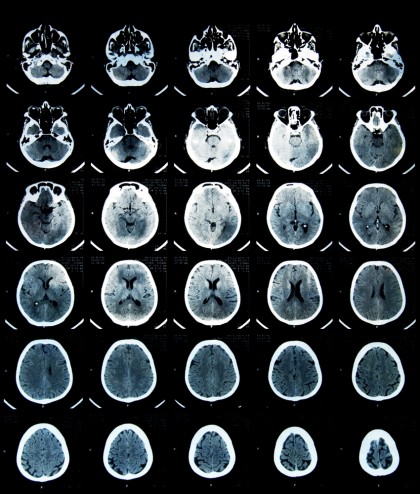

Anomalii cerebrale la pacienţii cu depresie şi anxietate

Dr. Sophia Frangou este autoarea studiului și este profesoară de psihiatrie la University of British Columbia. Pentru realizarea studiului, Frangou și echipa sa au colectat mai mult de 9.000 de scanări ale creierului din studii publicate anterior, care comparau activitatea creierului adulților sănătoși cu activitatea celor diagnosticați cu o tulburare de dispoziţie/ anxietate, ce varia de la depresie majoră la tulburare de stres post-traumatic. Cercetătorii au descoperit că pacienții prezentau o activitate cerebrală foarte scăzută în cortexul prefrontal și parietal inferior - regiuni cheie ale circuitului din creier pentru controlul emoțional și cognitiv. Aceste părţi ale creierului sunt responsabile, de asemenea, de încetarea anumitor activități mentale (aflate în desfășurare) și de trecerea la altele noi.

În plus, cercetătorii au descoperit o hiperactivitate în cortexul cingulat anterior, în amigdala stângă și în talamus, zone ale creierului care “„colaborează” pentru a procesa gândurile și emoţiile. Frangou intenționează să continue cercetările şi ia în considerare utilizarea unor metode non-invazive asupra unor regiuni ale creierului, care ar putea îmbunătăți calitatea vieţii pacienţilor care suferă de aceste tulburări psihice. Studiul este considerat a fi cea mai vastă analiză asupra creierului pacienților diagnosticaţi cu tulburări de dispoziție și anxietate de până acum.